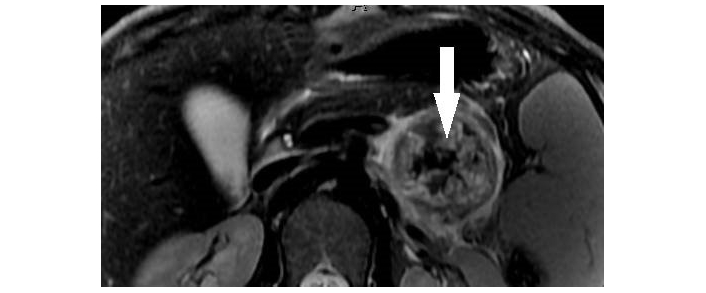

SPNs are characterized as a well-encapsulated thick-walled mass with varying solid, cystic, necrotic, and hemorrhagic components giving it a heterogeneous appearance. Hemorrhagic components of the lesion demonstrate higher than water attenuation on unenhanced CT and appear hyperintense on T1-weighted imaging. Solid components of the lesion show little enhancement on post-contrast imaging [26–28]. Peripheral/rim or septal calcifications may also be seen on CT scans, especially in larger lesions [29]. On MRI, the cystic components are T2 hyperintense while the characteristic thick capsule is T2 hypointense and demonstrates progressive delayed enhancement on post-contrast images (Figure 1) [30]. These features can help differentiate SPN from other PCL, such as SCA and MCN.

Solid pseudopapillary neoplasm of pancreas. Axial T2-weighted MR image demonstrates a partially cystic mass in the tail of pancreas with internal T2 hypointense hemorrhagic/solid components (arrowhead) and a hypointense capsule